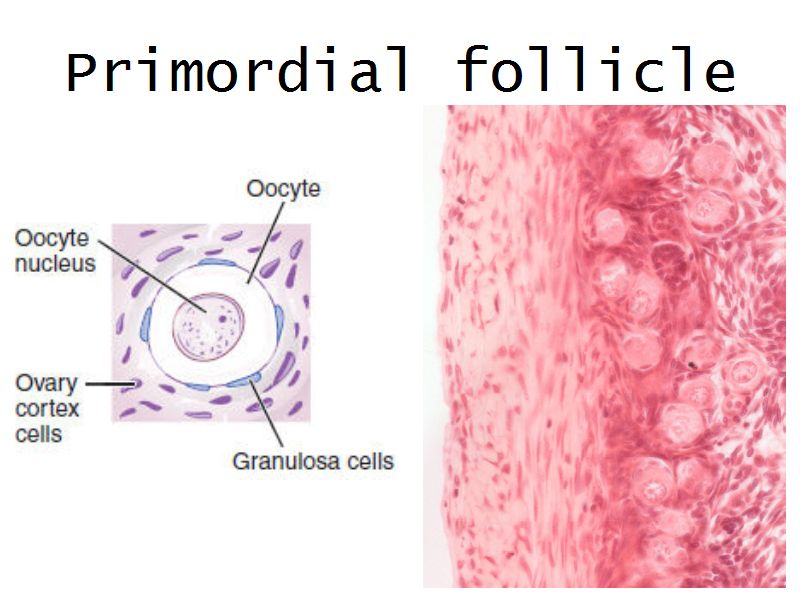

Follicular maturation

- Primordial follicle

- Growing follicle

- Primary follicle

- Secondary follicle

- Mature follicle (Graafian)

Components of a follicle

- Theca

- externa

- interna

- basal lamina

- Granulosa cells

- Antrum

- Cumulus oophorus >> Corona radiata

- Oocyte